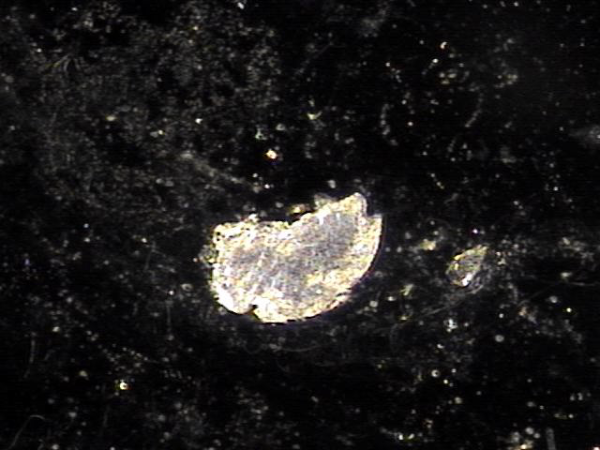

주 2~3회 정관의 표적 치료후 정관에 막혀 있던 상피 세포 덩어리가 치료된 현미경학적 자료입니다.

This is a microscopic image taken after targeted treatment of the vas deferens 2 to 3 times per week. It shows that the clumps of shed epithelial cells that had been blocking the vas deferens were successfully cleared.